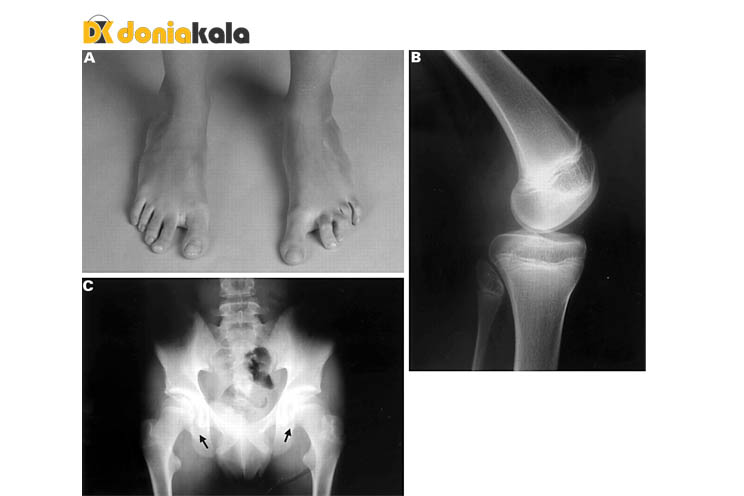

ناخن ها ممکن است از بین رفته، توسعه نیافته، تغییر رنگ، شکاف، برآمدگی یا حفره دار باشند. تصاویر بند انگشتی به شدت آسیب می بینند، به طوری که هر ناخن از انگشت اشاره تا انگشت کوچک کمتر تحت تأثیر قرار می گیرد. ناخن های پا معمولا کمتر تحت تاثیر این بیماری قرار می گیرند. کاسه زانو ممکن است از بین رفته باشد، کوچک باشد، شکل نامنظم داشته باشد و به راحتی جابجا شود، و ممکن است با کلیک، قفل یا احساس ناپایداری یا دردناک باشد.

لگن:

رشد استخوان روی استخوان لگن (که در اشعه ایکس قابل مشاهده است ) شایع است، اما معمولاً مشکلی ایجاد نمی کند.